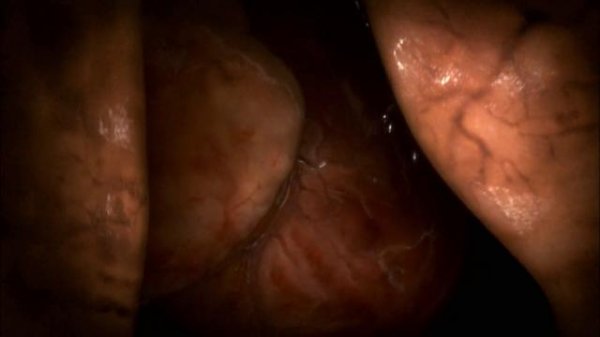

013906qoglzblob0plj9e9.jpg

013907s35b4bc04qbhhgg5.jpg